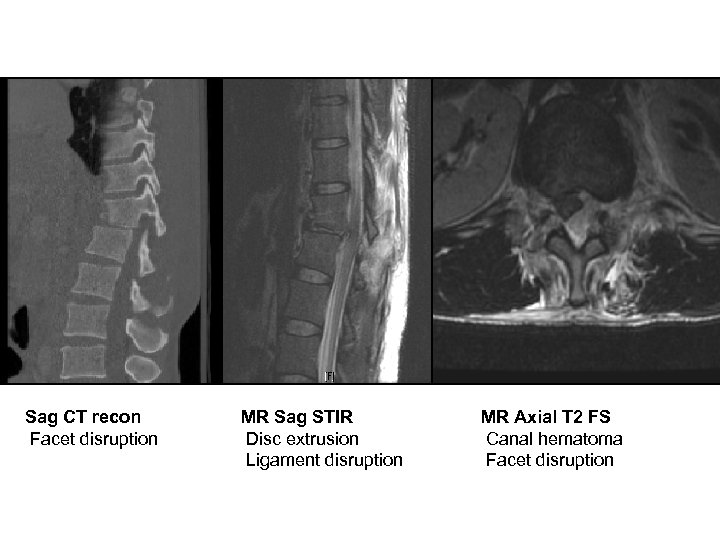

42 M fell from tree Motor - Full strength - Normal rectal tone Sensory - Intact to LT, proprioception, pin prick Reflexes - Normal at knees and ankles - No clonus 1 st degree instability TLICS 7 (4+0+3) ASIA E T 12

Sag CT recon Facet disruption MR Sag STIR Disc extrusion Ligament disruption MR Axial T 2 FS Canal hematoma Facet disruption

Post op result T 11 -L 2 posterolateral fusion Motor - Intact Sensory - Intact Bracing - TLSO Follow up - 6 week repeat X rays pending

Teaching points • Look beyond static image: What was the mechanism of injury? • Ligamentous injury >> bony injury • Ligamentous seat-belt-type fracture management options: – Open surgical instrumentation/fusion – Internal bracing (i. e. percutaneous instrumentation) – Bracing ?